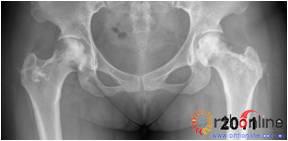

图2 男,22岁,激素性骨坏死,(1)双侧股骨头骨髓水肿,ARCO分期Ⅲa期,C3型;(2)X线片示股骨头塌陷,术前关节功能差(Harris评分50分);(3)打压植骨术(未加BMP2)后7年,关节功能好(Harris评分90分),股骨头有轻度塌陷,但头臼匹配好;(4)蛙式位显示股骨头臼匹配好